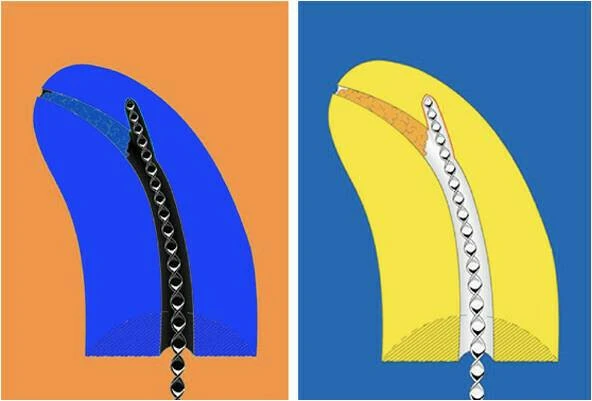

Hình bên dưới minh họa cho trường hợp sửa soạn bằng trâm K làm bằng thép không rỉ. Hình nảnh ống tủy bị dịch chuyển. Chú ý phần màu hồng là phần mô không được loại bỏ đầy đủ.

Trong hình minh họa bên dưới (a) là hình ảnh ống tủy bị làm thẳng và thủng thành; (b) Sự tạo khấc tại vị trí bắt đầu của đoạn cong và mất chiều dài làm việc.